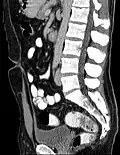

Additional images